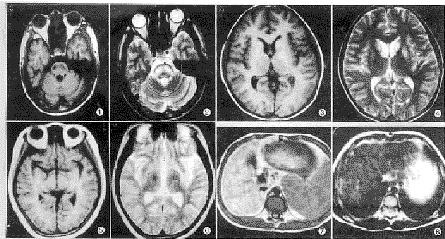

脑部检查病例中,9例脑部有异常信号,其病变部位:累及范围较对称和广泛,其中豆状核8例(88.9%),尾状核8例(88.9%),丘脑5例(55.6%),脑干1例(11.1%),半卵圆区1例(11.1%)。病变信号:多呈斑片状,边界较清,信号均匀,6例T1WI呈等低信号,T2WI多呈高信号(图1、2);1例尾状核和豆状核T1WI及T2WI均呈高信号(图3、4);1例下丘脑T1WI呈等信号,T2WI呈低信号(图5、6)。7例有轻度或中度脑萎缩,表现为脑室扩大及脑沟和脑池增宽,均表现较广泛。2例增强无异常强化。

腹部检查病例中,8例肝脏有异常信号,其病变部位左右叶均累及,表现为肝内大量弥漫性结节状异常信号,信号不均匀,边界不清,T1WI呈高信号或稍高信号,T2WI呈低信号(图7、8)。1例肝脏变形伴脾静脉扭曲扩张和腹水。17例有不同程度的脾脏肿大。所有病例肾脏均无异常。

图1 T1WI:脑干低信号 图2 T2WI:脑干高信号 图3 T1WI:双侧尾状核高信号 图4 T2WI:双侧尾状核及左侧豆状高信号 图5 T1WI:下丘脑等信号 图6 T2WI:右侧下丘脑低信号 图7 T1WI:肝内结节状高信号脾大 图8 T2WI:肝内结节状低信号